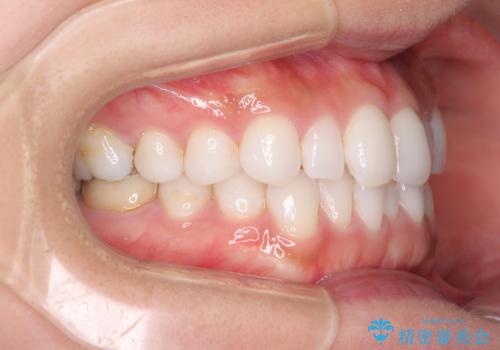

軽度の叢生をインビザライン・ライトで解消

- 前歯が気になるとのことで来院された患者様です。

歯列不正は軽微であったため、インビザライン・ライトにより、費用を抑えて矯正治療を行うこととしました。

短期間で気になる前歯の歯列を改善することができました。